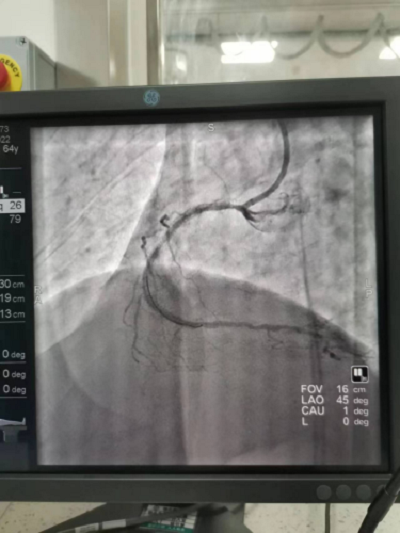

义诊高峰期,急诊科来了位急性下壁心肌梗塞的患者,涂小明主任立即安排好部分人员继续义诊,同时带领介入室团队回医院开展急诊手术,经过一个小时的抢救,成功地为病人开通了堵塞的血管 ,让心脏重获血液供应。

心脏介入导管室配备美国GE数字减影血管造影机(DSA),主动脉球囊反搏系统及临时起搏器,能24小时全天候开展冠脉介入诊疗、心律失常射频消融、单双腔心脏起搏、外周血管造影及支架植入等一系列高难度三四级手术。